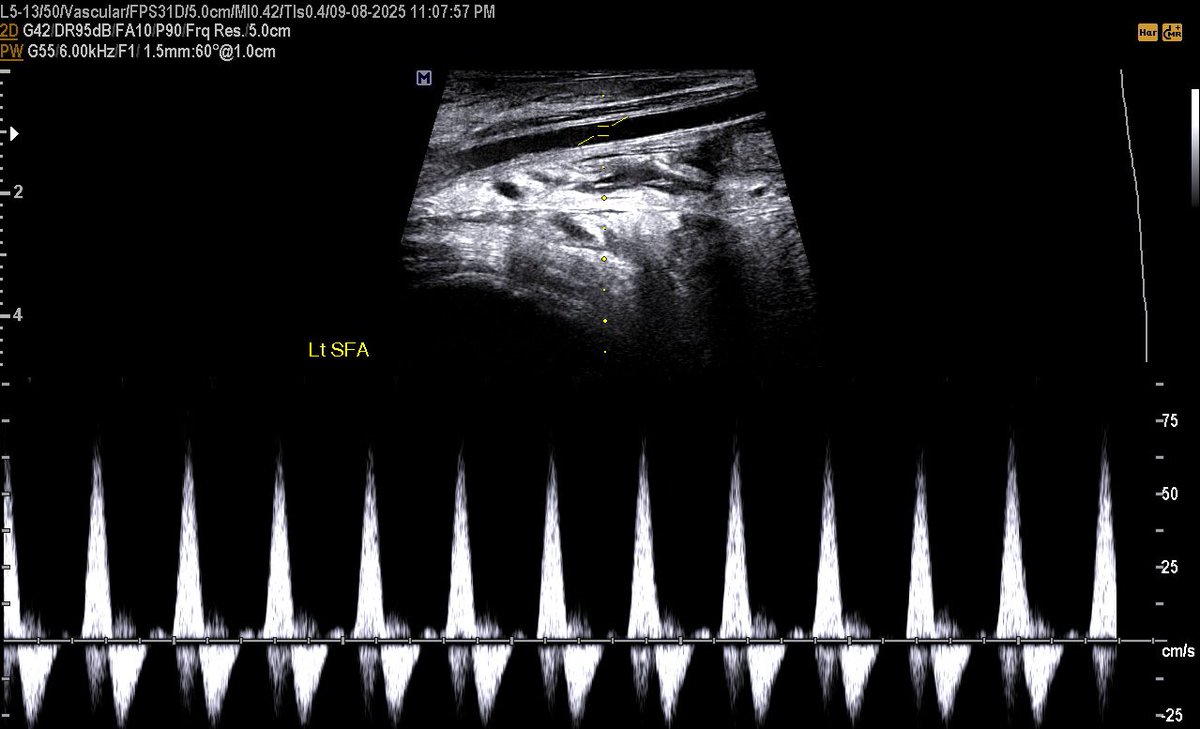

a 58 years male came with a diabetic foot And diffuse foot swelling Duplex U/S requested and done Your opinion? #EchoTech

a 58 years male came with a diabetic foot And diffuse foot swelling Duplex U/S requested and done Your opinion? #EchoTech

a 58 years male came with a diabetic foot And diffuse foot swelling Duplex U/S requested and done Your opinion? #EchoTech

a 58 years male came with a diabetic foot And diffuse foot swelling Duplex U/S requested and done Your opinion? #EchoTech